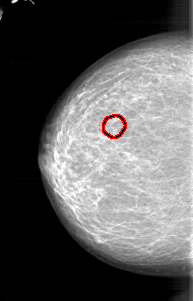

A_1235_1.LEFT_MLO

FILE: A_1235_1.LEFT_MLO.OVERLAY

TOTAL_ABNORMALITIES 1

ABNORMALITY 1

LESION_TYPE CALCIFICATION TYPE PLEOMORPHIC DISTRIBUTION CLUSTERED

ASSESSMENT 4

SUBTLETY 2

PATHOLOGY MALIGNANT

TOTAL_OUTLINES 1

BOUNDARY